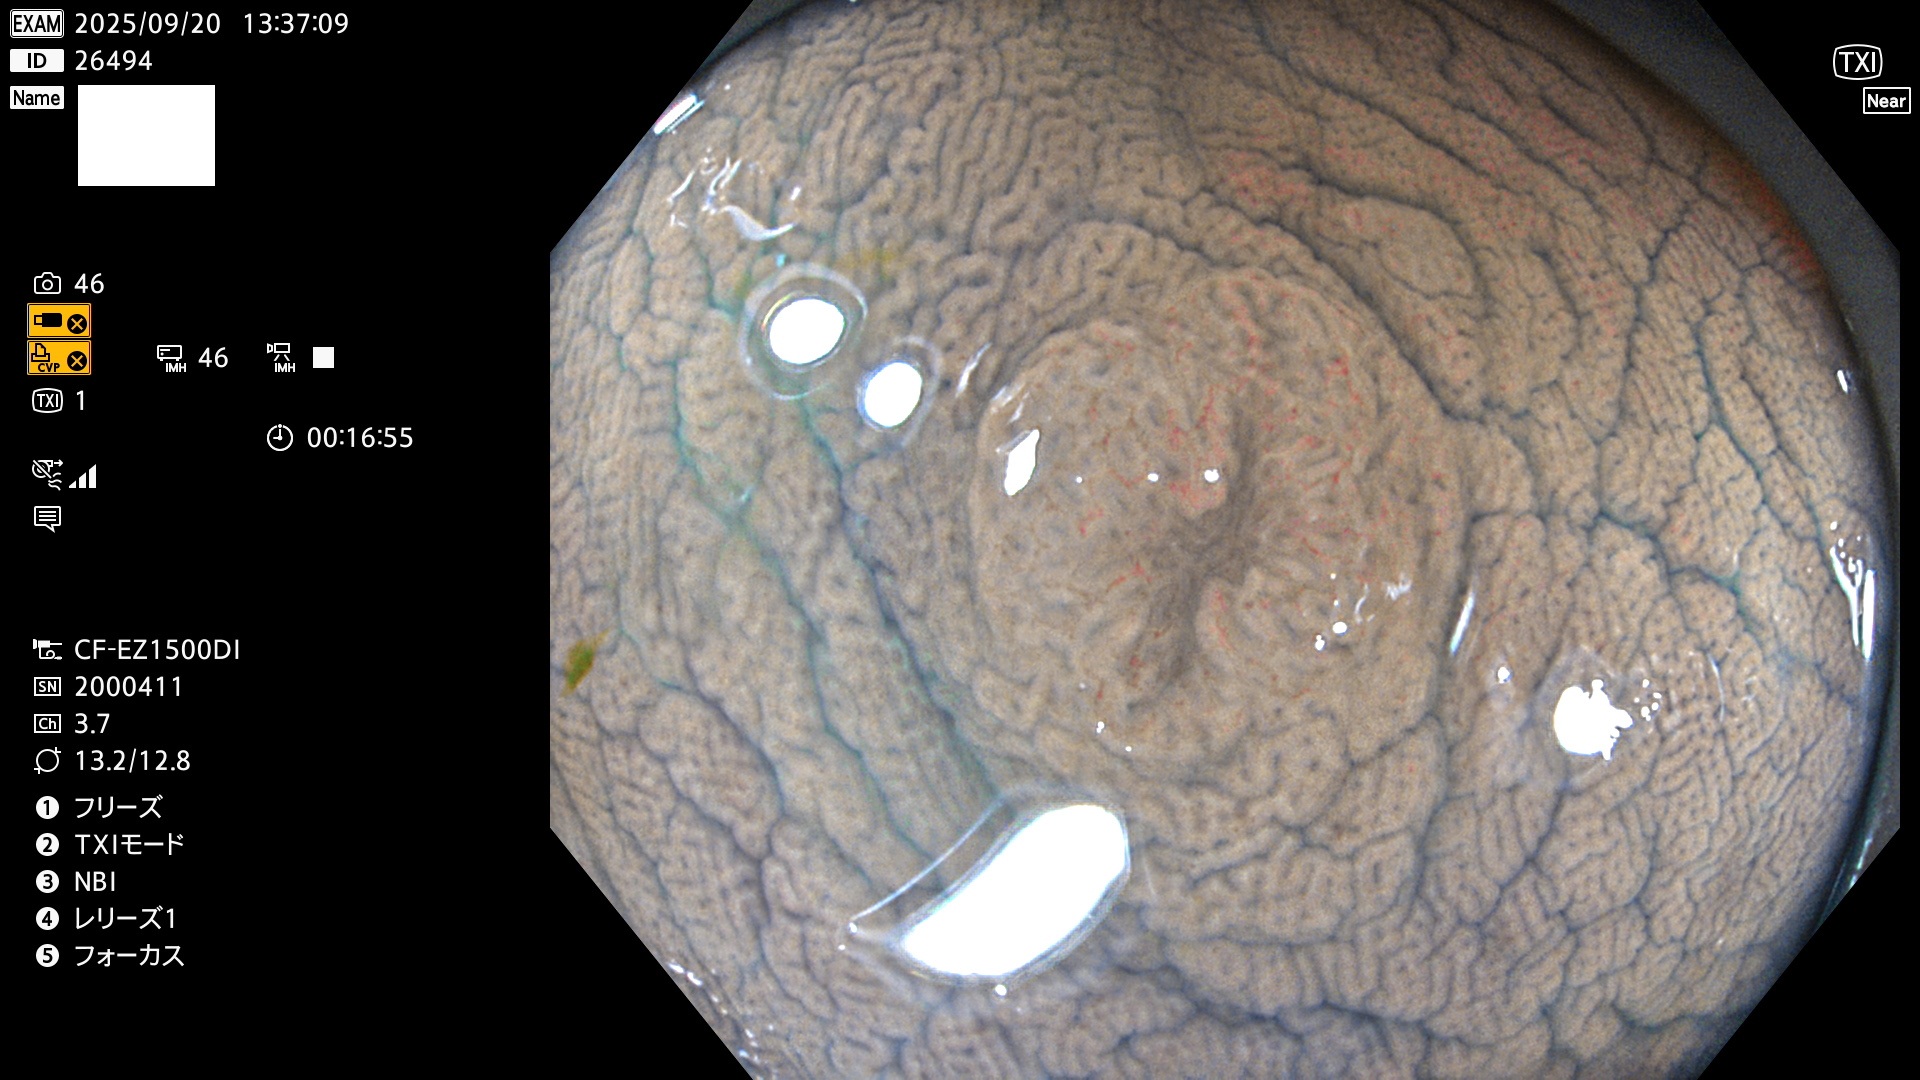

完全に平坦な物をUb、陥凹している物をUcと呼びます。Ubは認識が困難で、Ucはびらん(炎症)と紛らわしいために見落とされやすく、「内視鏡後・大腸癌」の原因になります。

専門的)Uc=De Novo癌? 内視鏡の解像度が低かった時代、このような説もありました。しかし今日の高精度内視鏡では良性の微小なUc型腺腫(APC遺伝子異常の腺腫)が日常的に見つかります。Ucこそが多段階発癌(Adenoma-Carcinoma Sequence)のMain Routeです。

毎週の検査(木・金・土・日)に発見されたUbとUc型・腺腫を、その週の日曜の夜にUPし1週間、提示します。

2025年9月17日〜9月21日の4日間(40件)6個 (Uc_ADR=6個/40人=15%)